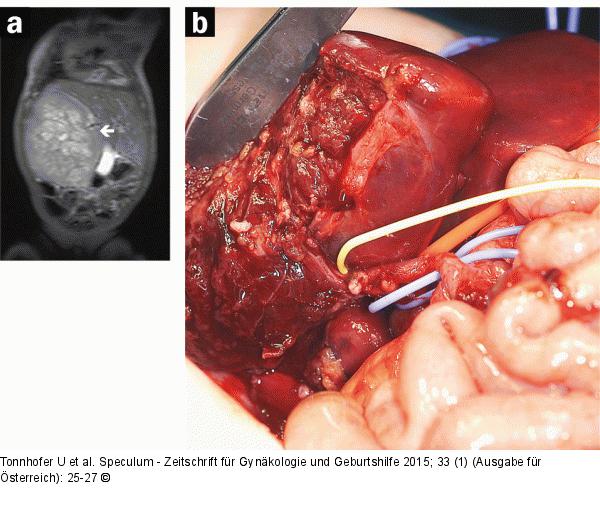

Abbildung 8a-b: Pränataldiagnostik-Therapie (a) Postnatales MRT Lebertumor; (b) OP-Situs. |

Abbildung 8a-b: Pränataldiagnostik-Therapie

(a) Postnatales MRT Lebertumor; (b) OP-Situs. |